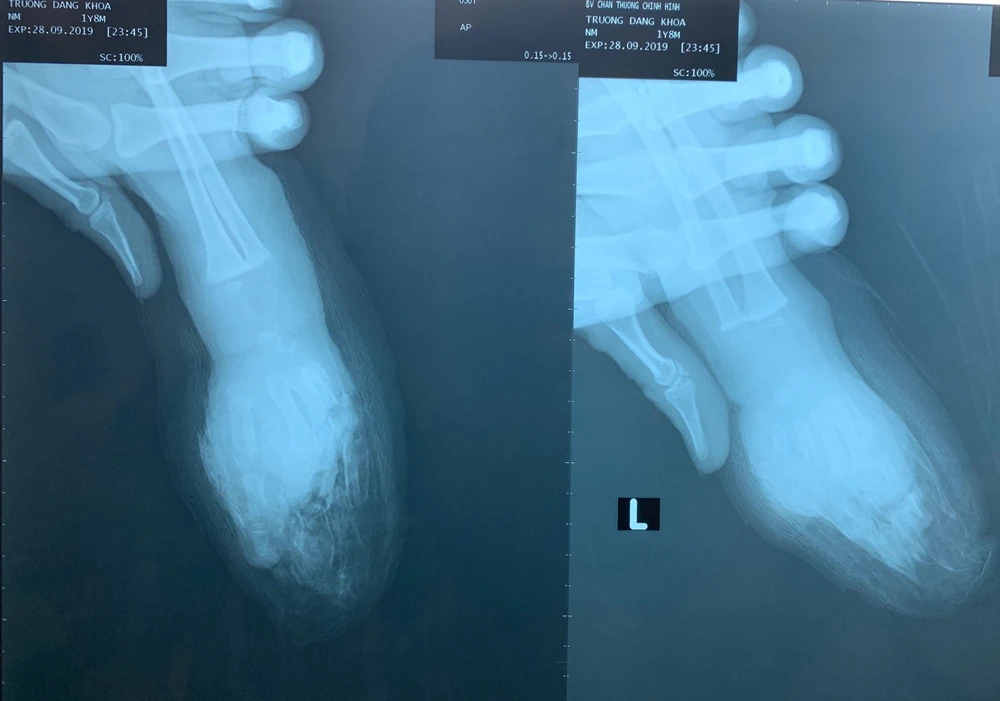

Trước đó, BV tiếp nhận bé K. trong tình trạng đứt lìa ngang giữa bàn tay trái. Các ngón 2, 3, 4 và 5 của bàn tay bị đứt lìa, vết thương bầm dập nhiều.

Giữa bàn tay trái cùng bốn ngón tay bé K. bị đứt lìa. (Ảnh do BV cung cấp)

Các bác sĩ cắt rửa lọc vết thương và nối vi phẫu bốn ngón tay dưới kính hiển vi. Sau đó tiếp tục phẫu thuật nối phần ngang giữa bàn tay. Ca mổ thành công sau 8 tiếng.